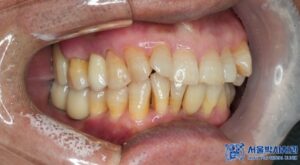

환자분은 처음 내원하셨을 때

흡연자였고 잇몸 상태가

전반적으로 좋지 않았습니다.

하지만 저희가 내원하실 때마다 금연의 중요성을

강조드렸고 실제로 수술을 받으신 후로는

많이 자제하셔서 회복도 매우 잘 되셨고,

현재는 임플란트를 아주 잘 사용하고 계십니다.